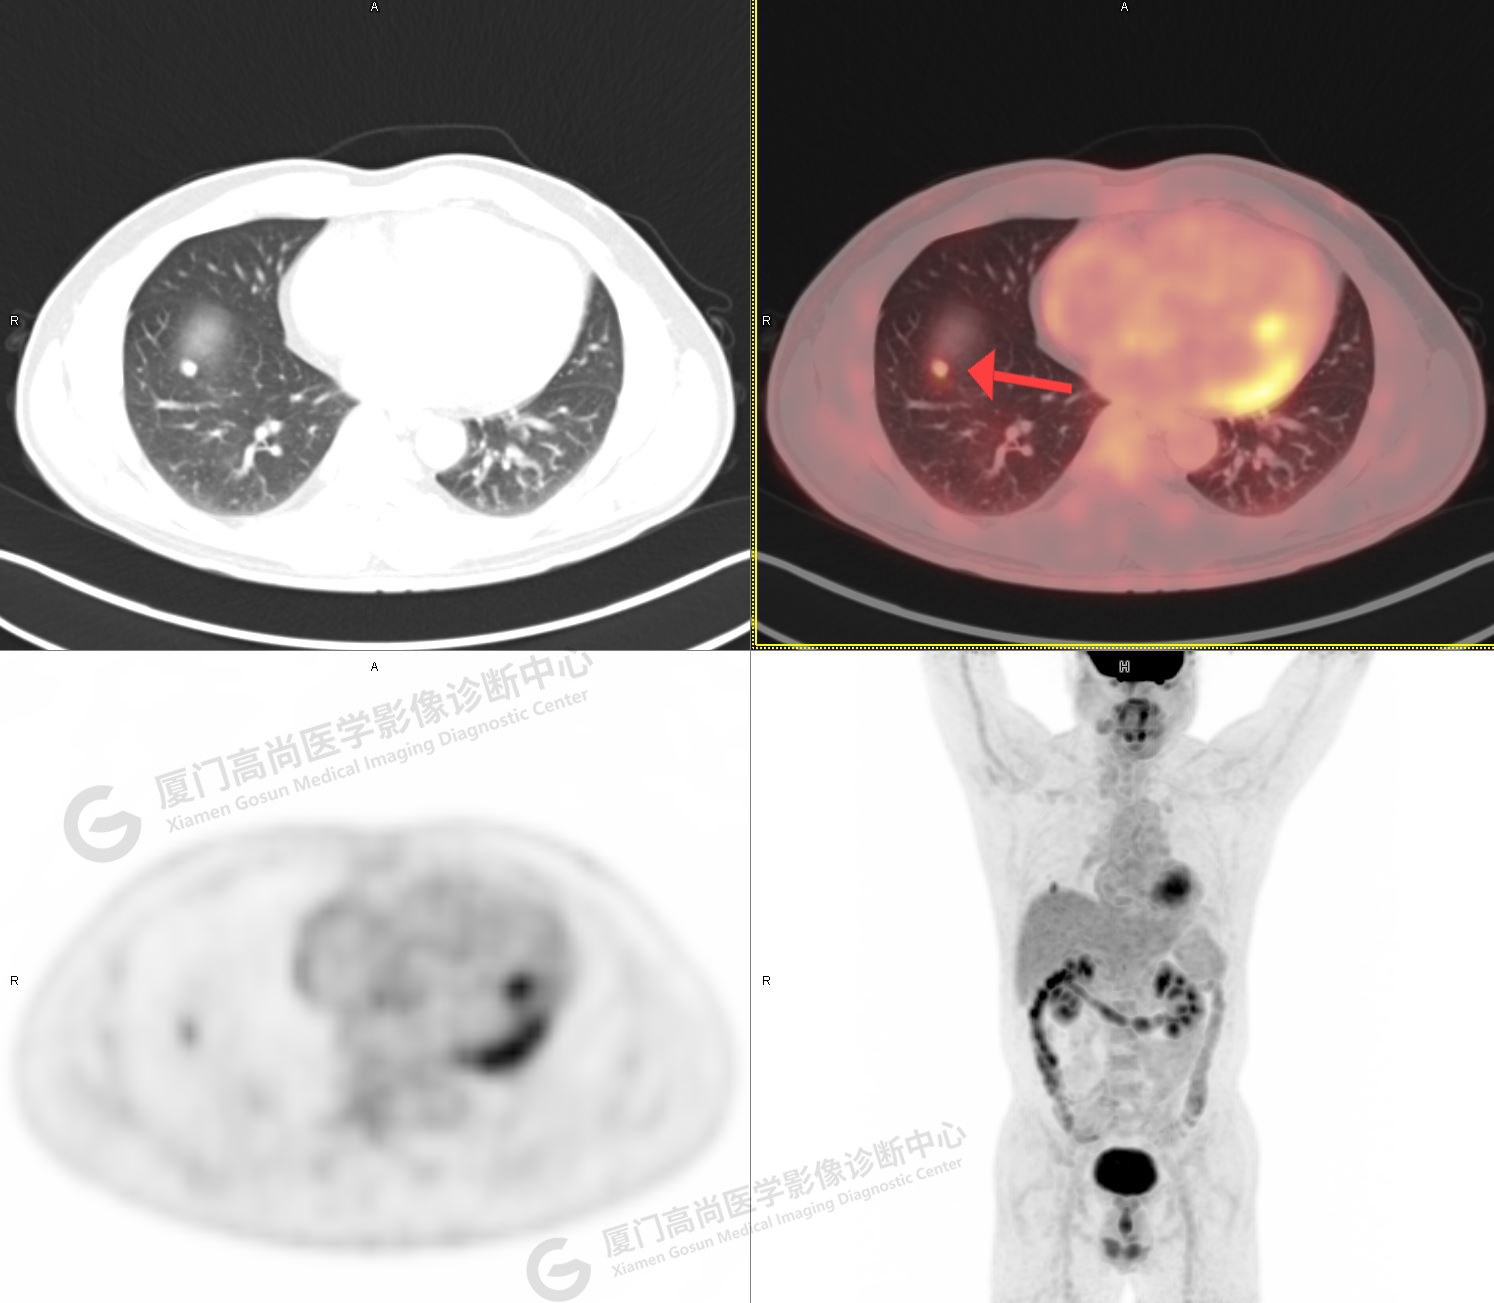

PET/CT影像圖

圖1

圖2

PET/CT示:右肺上葉尖段混雜密度結(jié)節(jié),代謝不高,考慮為早期肺癌(微浸潤腺癌),建議病理學(xué)檢查。

病理證實(shí)是肺腺癌。